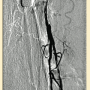

Peripheral angiography showed total occlusion of the right distal superficial femoral artery extending into the popliteal artery and into the trifurcation, with reconstitution of a peroneal and a posterior tibial. We attempted to obtain antegrade access to the lesions of the right infra-popliteal vessels (Figure 1). After failing to cross the lesion, we obtained retrograde access, puncturing from below the lesion through the posterior tibial artery near the ankle joint (Figure 2). Access was obtained and the lesion below the knee was crossed (Figure 3). Following this, the V-18 control wire (Boston Scientific) was snared from above, a CXI support catheter (CSI) was backloaded over the wire, and an antegrade Viperwire (CSI) was then placed, with removal of the retrograde sheath and wire. Atherectomy was performed with the 1.5mm Stealth 360° orbital atherectomy device (CSI) followed by balloon angioplasty with Cook, Sterling (Boston Scientific), and Chocolate (Cordis) balloon catheters. After angioplasty, significant improvement in luminal gain was noted at the expense of a dissection (Figure 4). We chose to place a Zilver PTX drug-eluting stent (Cook) within the distal superficial femoral and popliteal artery segment (Figure 5). After the procedure, the patient’s wounds completely healed. An angiogram 3 months later was performed, showing the vessels to be widely patent (Figure 6). The patient sent us a video of himself finally walking, and without pain (Video 1; online).